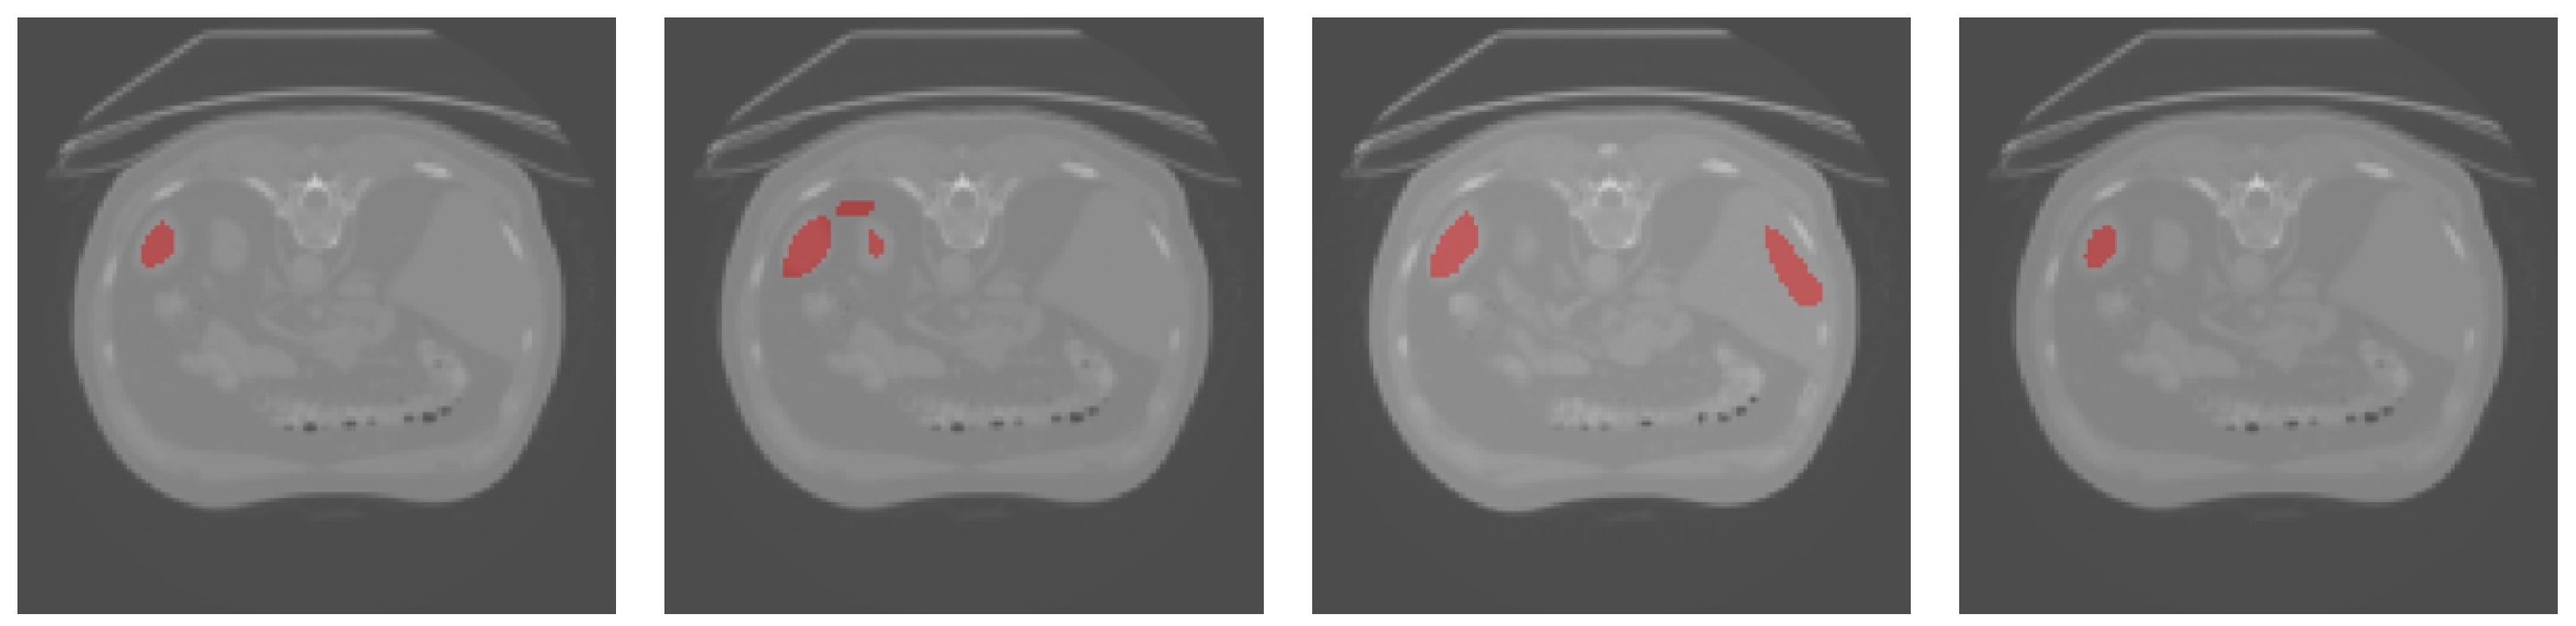

Figure 4 and Figure 5 show the results of a qualitative comparison of U-Net and Att-UNet with the proposed method, respectively. SAB-Net could capture higher semantic similarities and long-range relationships. Figure 5 demonstrates that some categories misclassified by U-Net and Att-UNet were correctly classified by our proposed method.

Figure 4.

Qualitative results obtained for the spleen CT images. From left to right: ground truth, U-Net, Att-UNet, and SAB-Net.